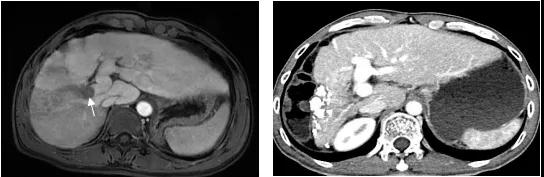

图3、该例大于15cm的巨大肝癌,经过2次DEB-TACE联合FOLFOX HAIC治疗,肿瘤明显缩小和肿瘤完全坏死。